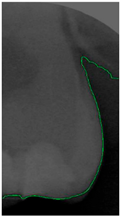

Dental calculus is recognized as a mineralized biofilm that comprises diverse calcium phosphate crystals, which may accumulate on the root surface both supra- and subgingivally [5]. A positive correlation between calculus deposits and periodontitis has been confirmed in multiple studies [6,7]. Despite clear evidence that the surface roughness of calculus alone does not initiate gingivitis, it is important to emphasize that calculus is consistently covered by an unmineralized layer of a viable biofilm [8], which is a primary factor in gingival inflammation [9]. The characteristics of dental calculus are not obvious in a BW image, as shown in Figure 1. The mechanical removal of subgingival plaque and calculus stands as the gold standard in the treatment of periodontitis [10]. While supragingival calculus can easily be seen and removed through sonic/ultrasonic instruments, subgingival calculus is invisible during intra-oral examination. Therefore, the identification of subgingival calculus is critical for the diagnostic process. Radiographic images have been widely used across various applications in the dental field [11]. Subgingival calculus is generally detected during periodontal probing, while radiographic examination can only show calculus on the proximal surfaces [12,13]. Meanwhile, Buchanan et al. [14] reported that the detection of dental calculus on the root surface by radiography had shown low sensitivity but high specificity, and a manual diagnosis can only detect dental calculus in 44% of the 275 datasets that truly have the condition. The detection ability can be increased to 82.2% by staining teeth with 1% methylene blue [15]. Galal et al. [16] observed that periapical films and intra-oral surveys showed comparable efficacy in calculus detection, with a particularly significant enhancement in detection when supplemented with radiographs. In comparison, other dental conditions like caries and periodontal disease have higher detection rates with manual methods. The detection rate for caries is approximately 70–85%, and for periodontal disease, it is around 65–80% [1]. Subgingival calculus documentation is crucial for periodontal assessment. Although clinical assessments are more common for detecting calculus, utilizing BW radiographs offers several advantages in calculus assessment. Firstly, BW images provide a comprehensive view of the tooth structure, allowing for a more thorough examination of interdental spaces where calculus often accumulates. Additionally, BW radiographs enable dentists to visualize areas that may be difficult to access during a clinical examination such as posterior regions. This enhanced visualization can aid in the early detection of calculus, leading to timely interventions and improved patient outcomes.

Figure 1.

Dental calculus symptoms on a BW image: (a) dental calculus symptoms; (b) absence of dental calculus symptoms.